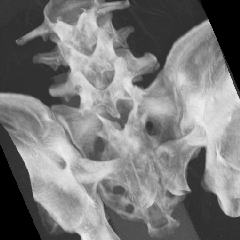

- MPR/MIP/MinIP/RaySum表示機能